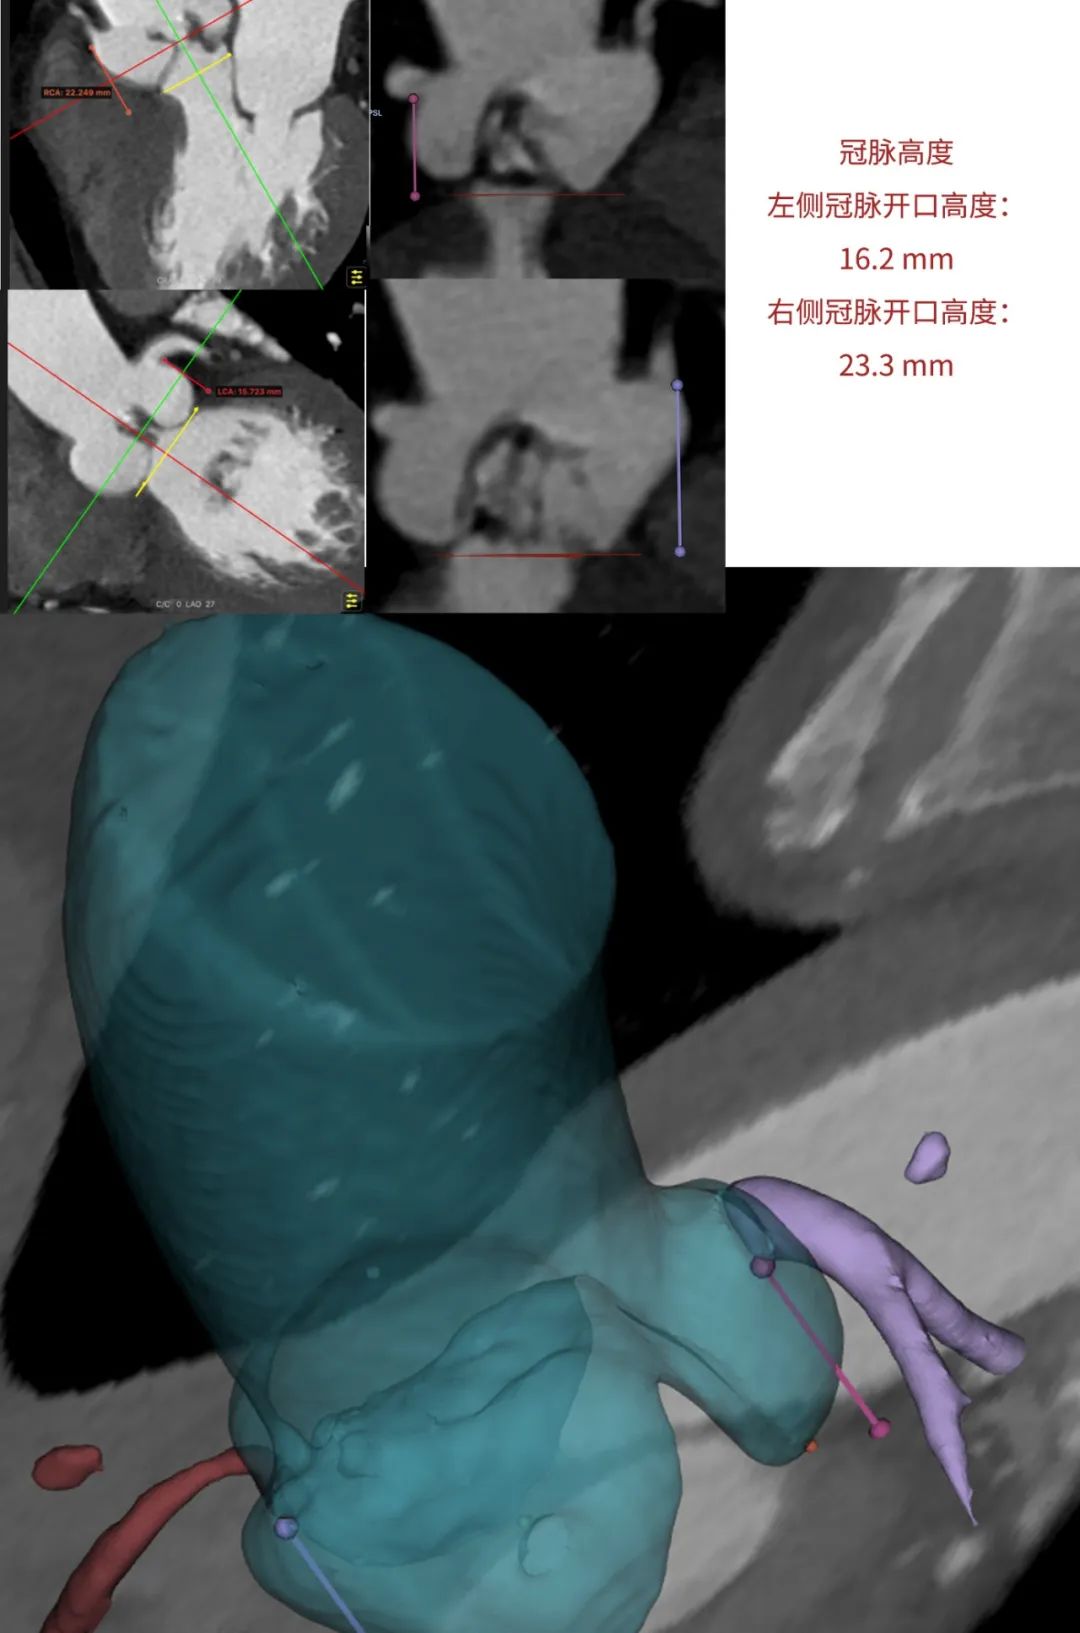

临床团队同时使用了基于医生手工描点的围术期影像评估软件和基于人工智能的瓣膜疾病围术期分析辅助决策软件进行术前影像学评估。

通过术前测量,对病例深入分析,结合人工智能术前分析辅助决策软件进行三维和二维图像融合,郭应强教授指出本例手术存在以下难点:

患者不到70岁,需要考虑远期冠脉保护。

在LAO 9 CAU 24(左右窦重合体位)投照角度,瓣叶交界贴合释放。